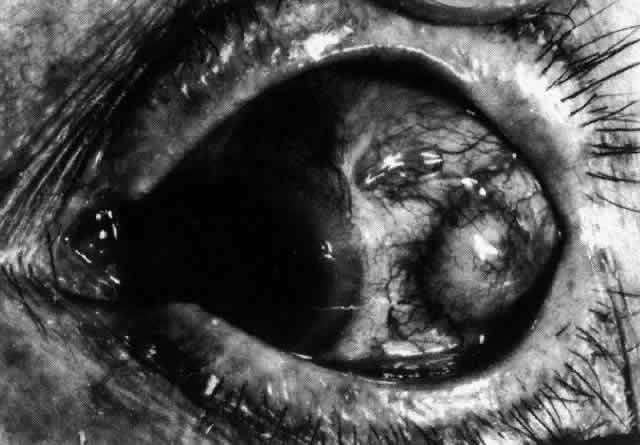

Nodular Anterior Scleritis

Although patients with nodular anterior scleritis resemble those with nodular episcleritis on cursory examination, detailed examination reveals marked differences. The nodule or nodules (they may be multiple) consist of scleral tissue that is immovable episclera is tightly adherent to the nodule, which is tender to the touch. Although the sclera sometimes becomes transparent below the nodule, it does not become necrotic, nor does the condition extend beyond the site of the nodule, as occurs in necrotizing scleral disease (Fig. 36).

(see Fig. 28; Figs. 34 and 35). The edematous

Fig. 34. Scleral edema has displaced all the vessel layers forward. Area surrounding the nodule is acutely inflamed.

Fig. 35. Multiple scleral nodules. Surrounding inflammation is deep and intense. (Watson PG: Management of scleritis. In: Recent Advances in Ophthalmology, Vol 5. London, Churchill-Livingstone, 1975)

The angiogram is similar to that of diffuse anterior scleritis (i.e., there is a rapid filling pattern and deep scleral leakage of dye).26